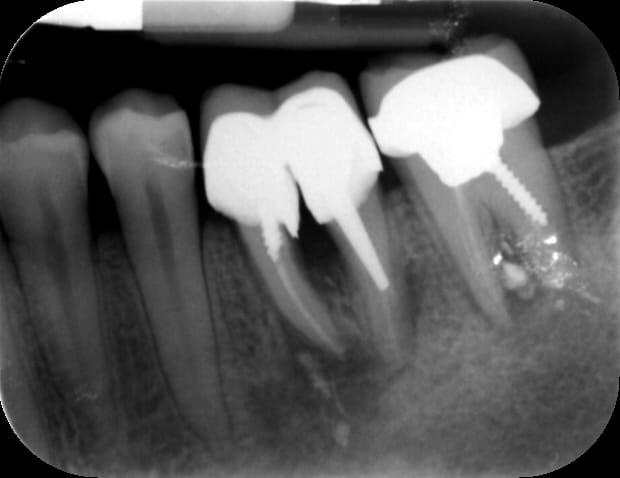

J'ai conclu par moi même qu'il fait de la merde en sur-équipant les patients , et récemment il fait de l'implanto . Voilà un superbe Not All on One , c'est un Ten On One . C'est beaaaaaauuu...)))

Img 3487 cuuqbi - Eugenol

Img 3488 h8ilol - Eugenol

Img 3489 cuhdog - Eugenol

Img 3491 pjrhic - Eugenol

Précision : Un correspondant et ami s'est chargé de l'extrimplantraction...car faut toujours avoir Dieu derrière soi pour combattre le diable devant les tribunaux . "Bin quoi ? Il était farpètement intégré mon implant , et dans le bon axe en plus !"